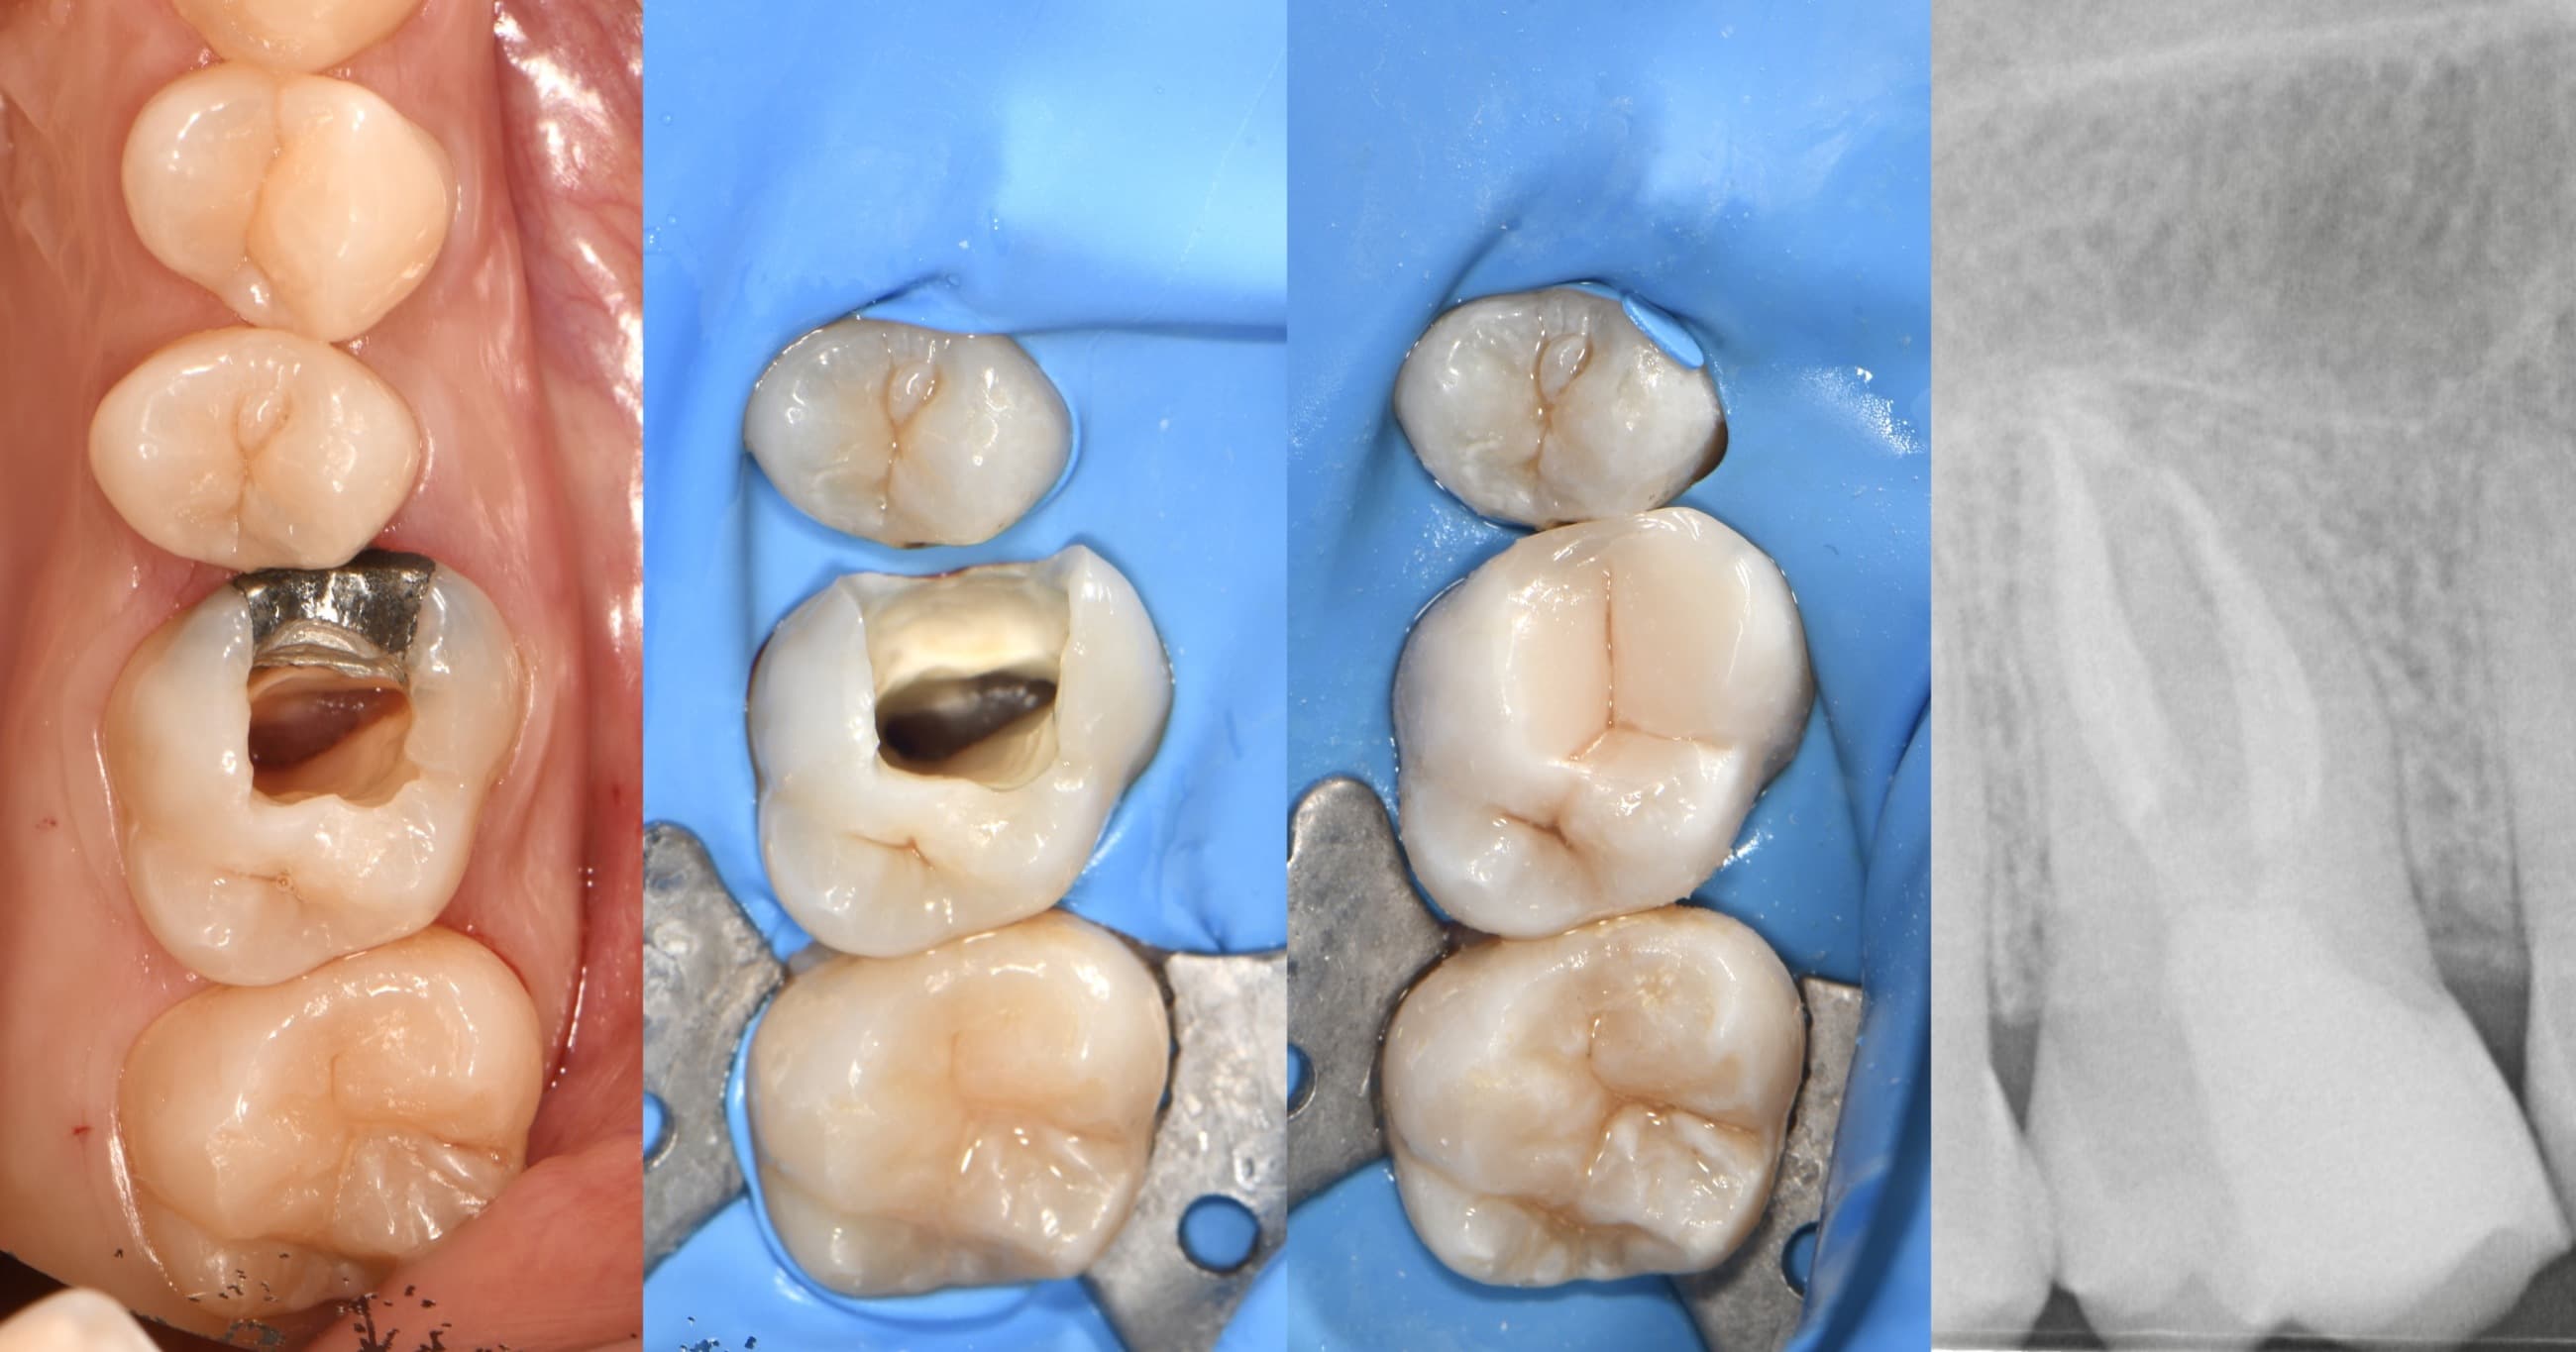

Rekonstrukce zubu 26 (nahoře vpravo) celokeramickou korunkou

Rekonstrukce zubu 36 (dole vlevo) celokeramickou korunkou